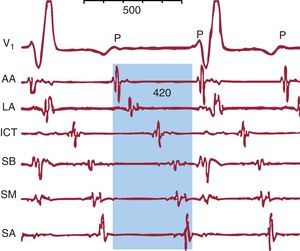

El AA típico, también llamado «común» por su frecuencia de presentación, destaca entre todas las TAMR por su dependencia de la estructura anatómica de la aurícula derecha (AD) y su clara identificación en el ECG4, pero otras TAMR resultan más difícilmente clasificables, especialmente en pacientes con antecedentes de cirugía cardiaca con atriotomías amplias o los que hayan sido sometidos a ablación amplia del miocardio de la aurícula izquierda (AI) para el tratamiento de la fibrilación auricular5. El ECG de una TAMR puede semejar una TAF con ondas P separadas por líneas de base isoeléctricas a frecuencias ≤ 200 lpm cuando hay zonas de conducción muy lenta en el circuito de reentrada, que generan potenciales de muy baja amplitud que no se detectan en el ECG de superficie, aunque sí en los registros intracardiacos (Figura 8). Por otro lado, una TAF puede producir un patrón de oscilación continua en el ECG si la LC es tan corta que se aproxima a la duración de la despolarización auricular (Figura 9).

Figura 8. Taquicardia auricular macrorreentrante con patrón electrocardiográfico de taquicardia auricular. V1 muestra ondas P regulares de bajo voltaje. Los registros endocárdicos de aurícula derecha anterior alta, lateral alta, septal baja, septal media, septal alta e istmo cavotricuspídeo muestran actividad eléctrica de muy bajo voltaje durante todo el ciclo de la taquicardia auricular macrorreentrante (sombreado azul) que el electrocardiograma no registra. AA: anterior alta; ICT: istmo cavotricuspídeo; LA: lateral alta; SA: septal alta; SB: septal baja; SM; septal media.

Patrón de activación auricularUna vez confirmado el mecanismo auricular, se hará una cartografía de activación auricular que determine la localización del foco de origen de una TAF (Figura 4, Figura 6, Figura 12) o la configuración anatómica de un circuito de TAMR, localizando el istmo o los istmos críticos cuya ablación permita interrumpirlo (figs. Figura 6 y Figura 11, Figura 12, Figura 13). La técnica de cartografía se basa en la medida de los retrasos de activación de múltiples puntos de una o las dos aurículas con respecto a una referencia temporal que puede ser el inicio de la onda P o un punto de registro endocárdico estable tomado como referencia 0 (arbitraria). La utilización de catéteres multipolares permite obtener varios registros simultáneos como referencia (Figura 15), monitorizar la estabilidad del circuito y revelar la proporción del ciclo cubierto por la activación auricular, que en la TAF suele ser < 50%, mientras que en la TAMR puede ser el 100% si se obtienen suficientes registros (figs. Figura 1, Figura 8, Figura 16, Figura 17). Cuando el foramen oval no es permeable, se puede hacer registros desde el seno coronario para obtener tiempos de activación próximos al anillo mitral inferior y desde la arteria pulmonar derecha para registrar la activación del techo de la AI (Figura 15), pero la cartografía detallada de la AI exigirá un cateterismo transeptal.